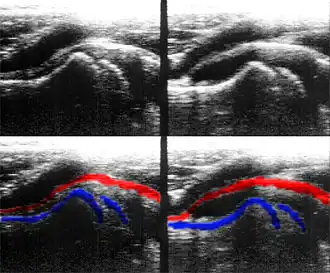

Die Aussagekraft der Sonografie kann erheblich durch die Anwendung des Doppler-Effekts erhöht werden. Man unterscheidet eindimensionale Verfahren (Pulsed-Wave-Doppler, Continuous-Wave-Doppler, auch als D-mode bezeichnet) von zweidimensionalen, farbkodierten Anwendungen (Farbdoppler – F-mode). Die Kombination B-Bild mit Pulsed-Wave-Doppler (PW-Doppler) nennt man auch Duplex.[4]

Doppler-Verfahren werden benutzt zur Bestimmung von Blutfluss-Geschwindigkeiten, zur Entdeckung und Beurteilung von Herz(klappen)fehlern, Verengungen (Stenosen), Verschlüssen oder Kurzschlussverbindungen (Shunts), siehe Farbkodierte Doppler-Sonografie.

Bei der farbkodierten Doppler-Sonografie wird für einen großen Bereich eines konventionellen Ultraschallbildes (Color-Window) die örtliche Doppler-Frequenz (= mittlere Flussgeschwindigkeit) und deren Schwankungsbreite bestimmt. Damit möchte man die Turbulenz der Strömung abschätzen. Aufgrund der statistischen Bewegungen der Streuteilchen ist die Schwankungsbreite der Fließgeschwindigkeit jedoch stets größer als die Turbulenz. Das Ergebnis wird in Falschfarben auf dem B-Bild überlagert, also in Farbtönen von rot und blau für verschiedene Blutgeschwindigkeit und grün für Turbulenz. Hierbei steht üblicherweise die Farbe Rot für Bewegung auf den Schallkopf zu, während mit blauen Farbtönen Flüsse weg von der Sonde codiert werden. Bereiche der Geschwindigkeit 0 werden durch die Elektronik unterdrückt.

-

Anwendung des Doppler-Verfahrens bei einer Herzuntersuchung: Mitralklappeninsuffizienz

Anwendung des Doppler-Verfahrens bei einer Herzuntersuchung: Mitralklappeninsuffizienz -

Farb-Doppler und PW-Doppler. Innerhalb der Stenose ist wegen der hohen Flussgeschwindigkeit und des resultierenden Alias-Effekts die Geschwindigkeit in Blau kodiert.

Farb-Doppler und PW-Doppler. Innerhalb der Stenose ist wegen der hohen Flussgeschwindigkeit und des resultierenden Alias-Effekts die Geschwindigkeit in Blau kodiert. -